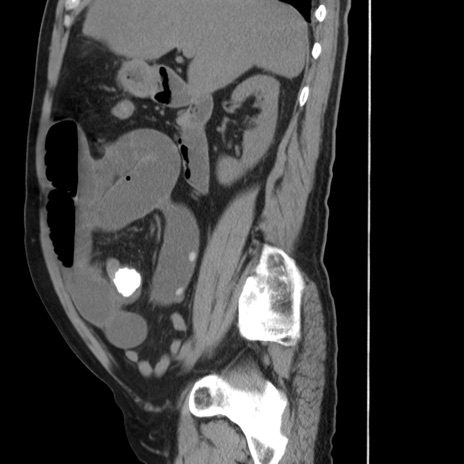

症例20(矢状断像)

【症例】 60歳代男性

【主訴】 腹部膨満、嘔吐

【現病歴】5日前頃より倦怠感を認め食事量減少し4日前の朝嘔吐、食事摂取困難となった。 3日前近医受診し点滴施行され整腸剤などを処方された。 当日他院を受診し、腹部膨満著明、炎症反応の上昇(CRP10.8、WBC11200)あり、紹介受診となる。

【身体所見】 意識JCS1 受け答えがはっきりしないBP 111/57mHg、 P 67bpm、、BT35.2°C、SpO2 97%(RA)、 腹部:膨隆、打診で鼓音あり、全体的に圧痛有り、腸蠕動音(-)、反跳痛ははっきりせず。

【データ】WBC 11400、CRP 14.20